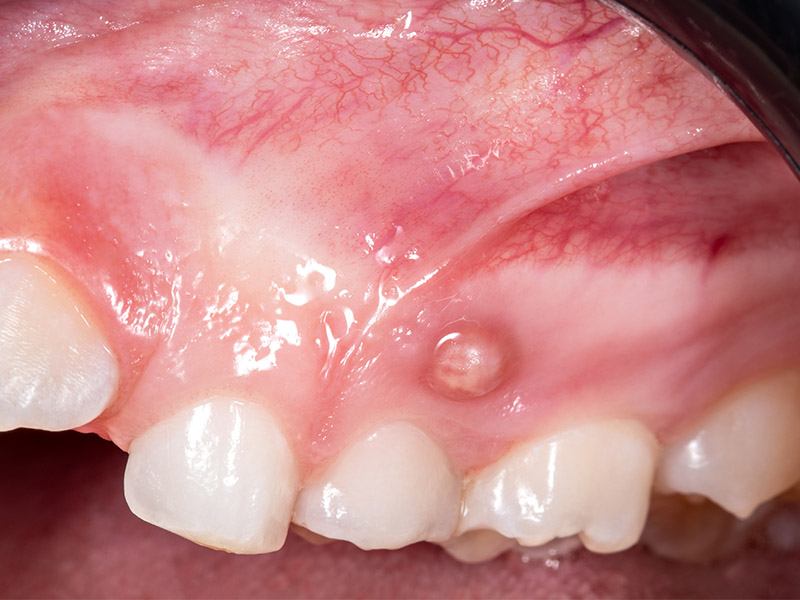

- Comparsa di fistole (piccole bollicine con fuoriuscita di liquido)

- Gonfiore della gengiva vicino al dente interessato